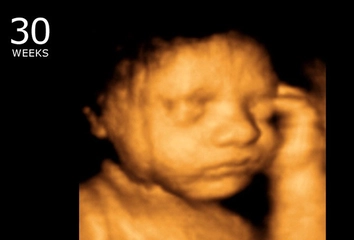

Gebelik, birçok fizyolojik değişikliklerin yanı sıra bazı komplikasyonları da beraberinde getiren bir süreçtir. Bu süreçte, kanama, hem anne hem de fetüs için önemli bir risk faktörü oluşturabilir. Gebelikte kanamanın nedenleri, erken dönem ve geç dönem şeklinde iki ana gruba ayrılabilir. Bu makalede, gebelikte kanamanın olası nedenleri üzerinde durulacak ve her bir nedenin klinik önemi ele alınacaktır. Erken Dönem Kanama NedenleriErken dönemde meydana gelen kanama, genellikle 20. gebelik haftasından önce gerçekleşir ve aşağıdaki nedenlere bağlı olarak gelişebilir:

Geç Dönem Kanama NedenleriGebeliğin ikinci ve üçüncü trimesterinde meydana gelen kanamalar, aşağıdaki nedenlerden kaynaklanabilir: